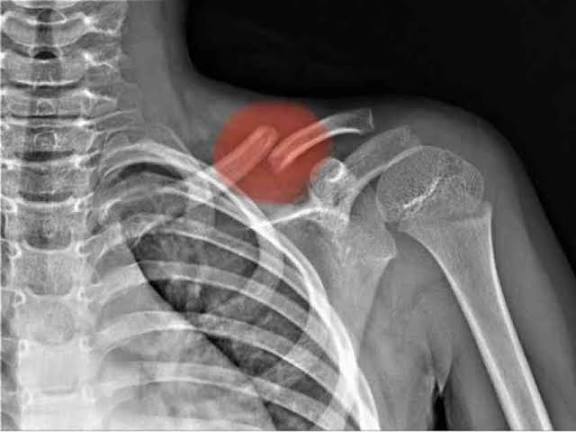

وترتبط الترقوة بعظمة القص ولوح الكتف وتشكل محور الحركة في مفصل الكتف. وعند الكسر، قد تنفصل أجزاؤها كليًا أو جزئيًا، مما يؤدي إلى:

كيف يتم تشخيص كسر الترقوة؟

يبدأ التشخيص بفحص سريري يتبعه تصوير بالأشعة السينية لتحديد:

ـ مكان الكسر

ـ نوعه

ـ مدى انفصال الأجزاء

وفي الحالات المعقدة يستخدم الأطباء الأشعة المقطعية قبل وضع خطة العلاج.